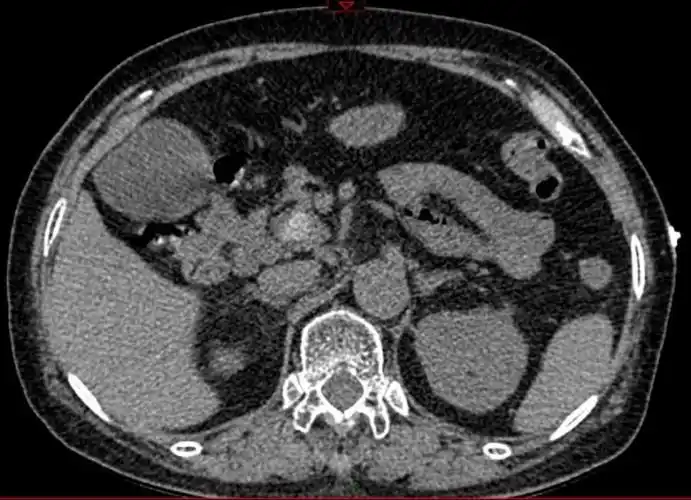

ct提示胆囊结石伴胆囊炎

ct横断面可见结石自下而上填满胆总管.

腹部ct提示:胆囊结石(箭头处)

行ct提示胆总管结石并胆道梗阻.(如图3)

胆管结石